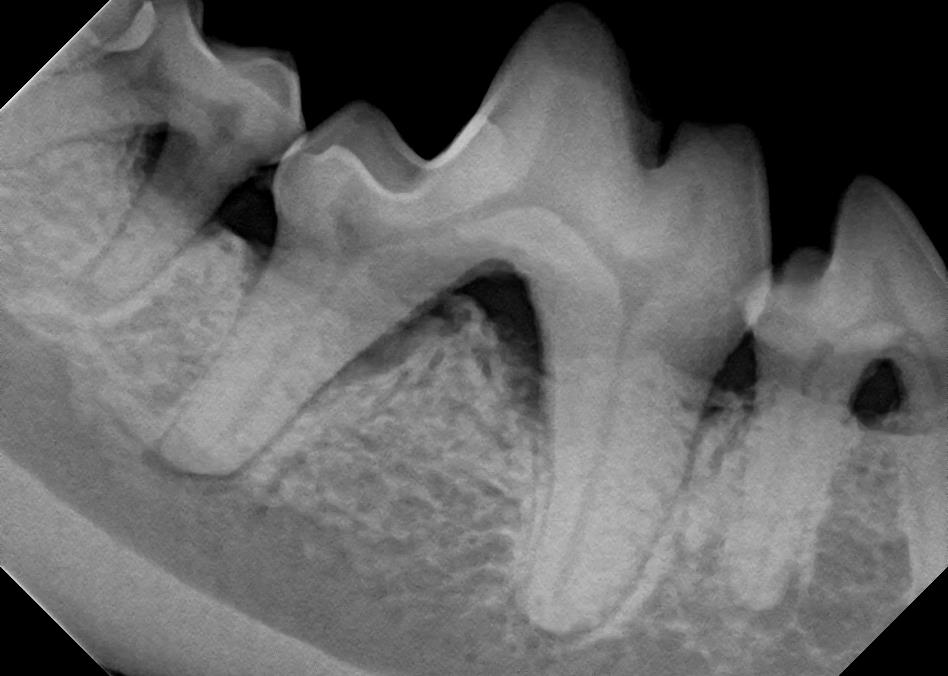

Examples of dental problems:

At A Couple of Vets, our animal hospital staff is well-versed in the latest dental cleaning techniques to remove plaque and tarter from the teeth’s surface as well as from below the gum line. We perform dental x-rays at every cleaning to ensure that the teeth are completely healthy. They may look good on the surface, but many problems occur below the gum line and are only visible with x-rays.